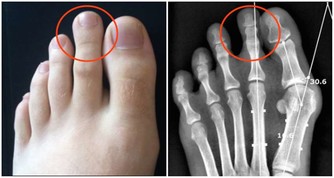

睡前泡腳也是一個容易讓心情放鬆、平靜,助於睡眠的習慣,睡前可以用微燙的熱水泡泡腳,水最好泡在足踝關節以上,直到泡到額頭微微出汗為宜。泡腳後,還可以再用手搓腳心10至20分鐘,直至發熱。臨睡前,用手指輕輕按揉眉頭和眉梢處,舒緩眼部,也能提高睡眠質量。有條件的話,睡前做做有氧健身走、進行中醫針灸治療、太極拳及按摩。這些都能幫助緩解心理壓力,進而擁有一個好睡眠。